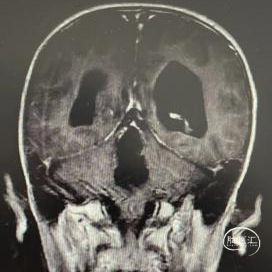

男,6岁,目光呆滞4天入院。

体查:步态稍不稳。

头部CT显示:小脑蚓部可见一不规则高密度肿块,大小41mm*30mm,可见多发片状钙化向椎管内延伸;脑桥、延髓、小脑均有受压,桥前池、第四脑室明显变窄。

头部MRI显示:小脑蚓部可见不规则等-长T1、等-长T2信号囊实性肿块,较大层面大小约40mm*32mm,增强后病灶可见明显不均匀强化,病灶内可见钙化灶,边界欠清。脑桥、延髓、双侧小脑及第四脑室受压,幕上脑室扩大。

病理检查:室管膜瘤(WHO2级),伴坏死,区域细胞增生活跃。Ki67(热点区5%+)。

枕下后正中入路全切除病变。术后建议放射治疗。

例1为室管膜瘤,病变内存在大量钙化,且不规则成块,内隐小血管供血引流。在切除肿瘤的过程中采取了更加激进的手术策略,将侵犯至左侧面丘的肿瘤予以锐性切除。术后发生一过性展神经麻痹。术后建议局部放射治疗。例2为髓母细胞瘤,肿瘤经左侧外侧孔长出四脑室,切除四脑室内肿瘤主体部分后再通过外侧孔将此区域肿瘤切除以降低肿瘤负荷,术后患儿未出现脑积水、缄默、偏瘫等严重并发症,情绪稳定,预计可以顺利进入辅助治疗阶段。患儿术前MRI发现有脚间窝小转移灶,应进一步检查脊柱脊髓全程,了解有无椎管内转移。例3为低级别胶质瘤,肿瘤经扩大之导水管向上生长,予以镜下全切除打通脑脊液循环通路。术后磁共振证实全切除后,予以严密观察定期随访。